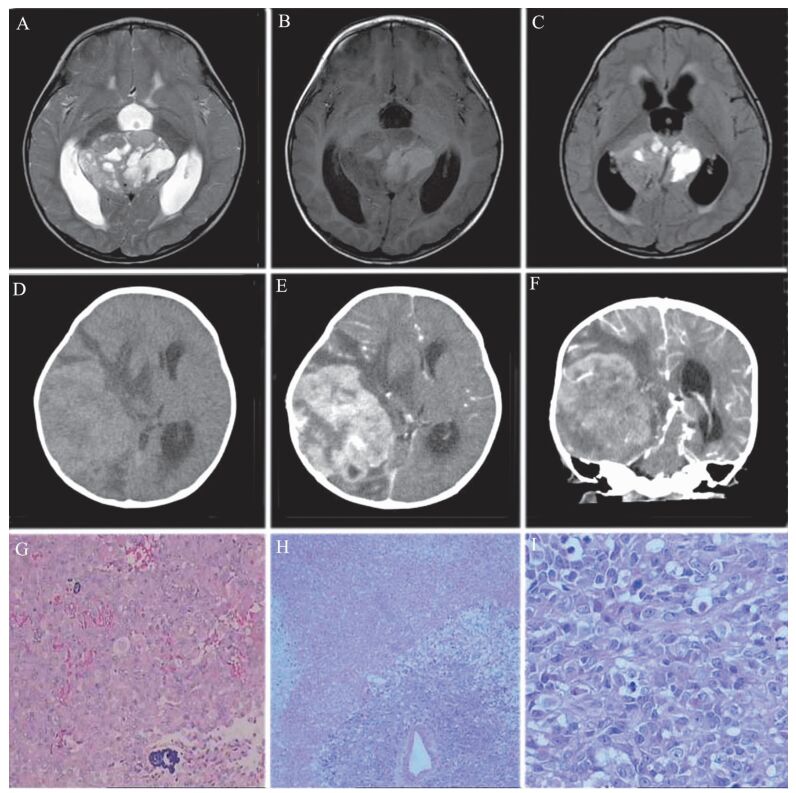

22例中16例(72.7%)行头颅MRI平扫+增强检查。5例(22.7%)行CT平扫+增强检查。16例MRI均显示占位性病变,均挤压周围组织造成压迫、梗阻,其中7例(43.8%)为囊实性病变、囊腔大小不一,9例(56.3%)为实性病变;16例MRI的T2加权像均显示为高信号,T1加权像显示为高、等或稍低信号,增强后肿块呈不均匀强化,见图 1A~C。22例CT均见不规则软组织密度肿块,增强后呈不均匀强化,见图 1D~F

图 1 一例中枢神经系统AT/RT患儿影像学及病理检查图 A:MRI的T2加权像;B:MRI的T1加权像;C:液体衰减反转恢复(FLAIR)序列;D:CT平扫;E~F:CT增强扫描;G:病理检查显示组织形态单一(苏木素-伊红染色,×100);H:病理检查显示组织形态多样化(苏木素-伊红染色,×100);I:典型的横纹肌样细胞(苏木素-伊红染色,×400)

22例手术切除组织镜检均可见典型的横纹肌样细胞,其中9例(40.1%)有不同程度的坏死,见图 1G。10例(45.5%)组织形态多样,表现为肿瘤细胞弥漫成片排列,从状血管增生,可见梭形细胞及透明细胞区域,亦可见腺样结构、菊形团及假菊形团形成,见图 1H。12例(54.5%)组织形态单一,表现为肿瘤细胞弥漫成片分布,部分围绕血管排列,肿瘤细胞形态大小较一致,肿瘤细胞边界清楚,核圆形,可见核仁,部分偏位,胞浆红染,呈横纹肌样,可见大量病理性核分裂,凋亡小体易见,见图 1I